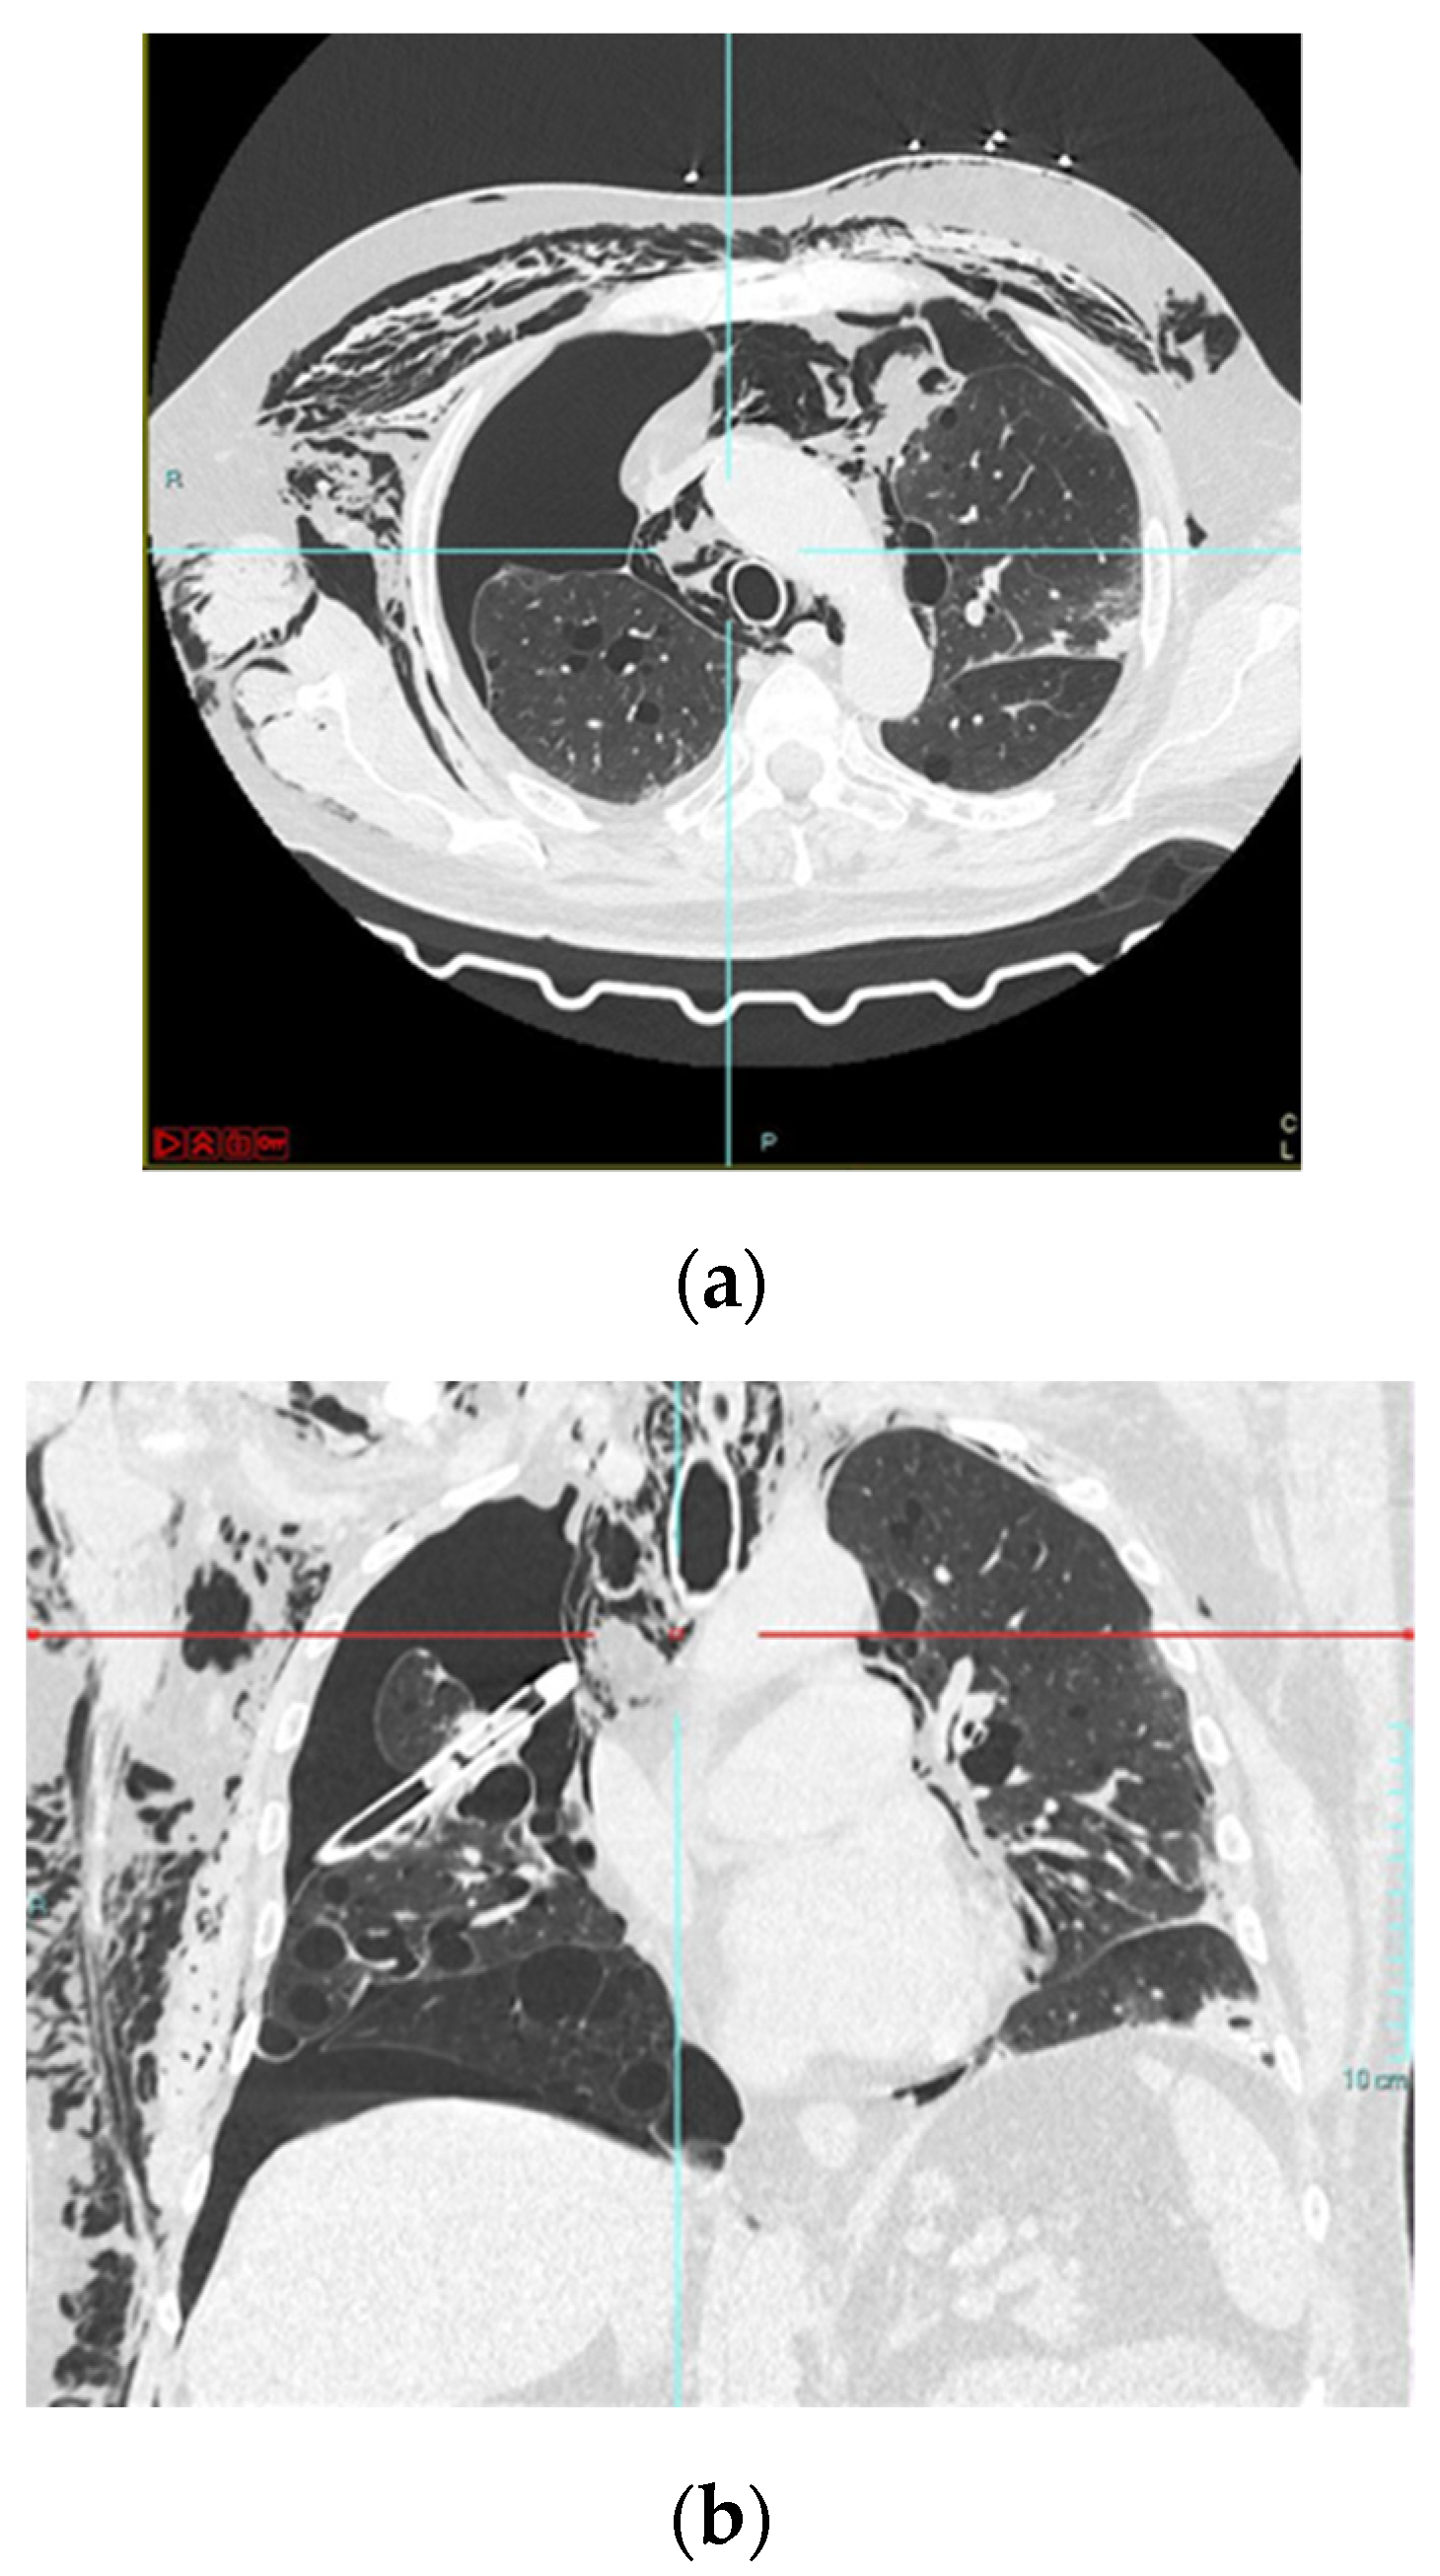

Pneumomediastinum and Pneumothorax as Relevant Complications of Sub-Intensive Care of Patients with COVID-19: Description of a Case Series

2. Description of Cases